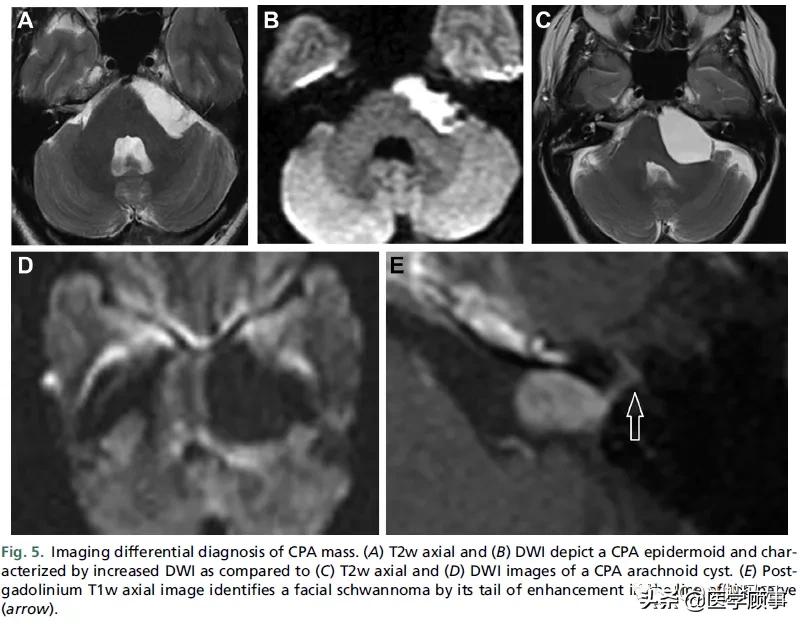

图5。CPA肿块的影像学鉴别诊断。(A) T2w轴位和(B) DWI显示CPA表皮样病变,与(C) T2w轴位和(D) DWI所显示的CPA蛛网膜囊肿相比,DWI增加。(E)钆剂增强后T1w轴位图像通过在神经线上其尾部的增强(箭头)识别面神经神经鞘瘤。